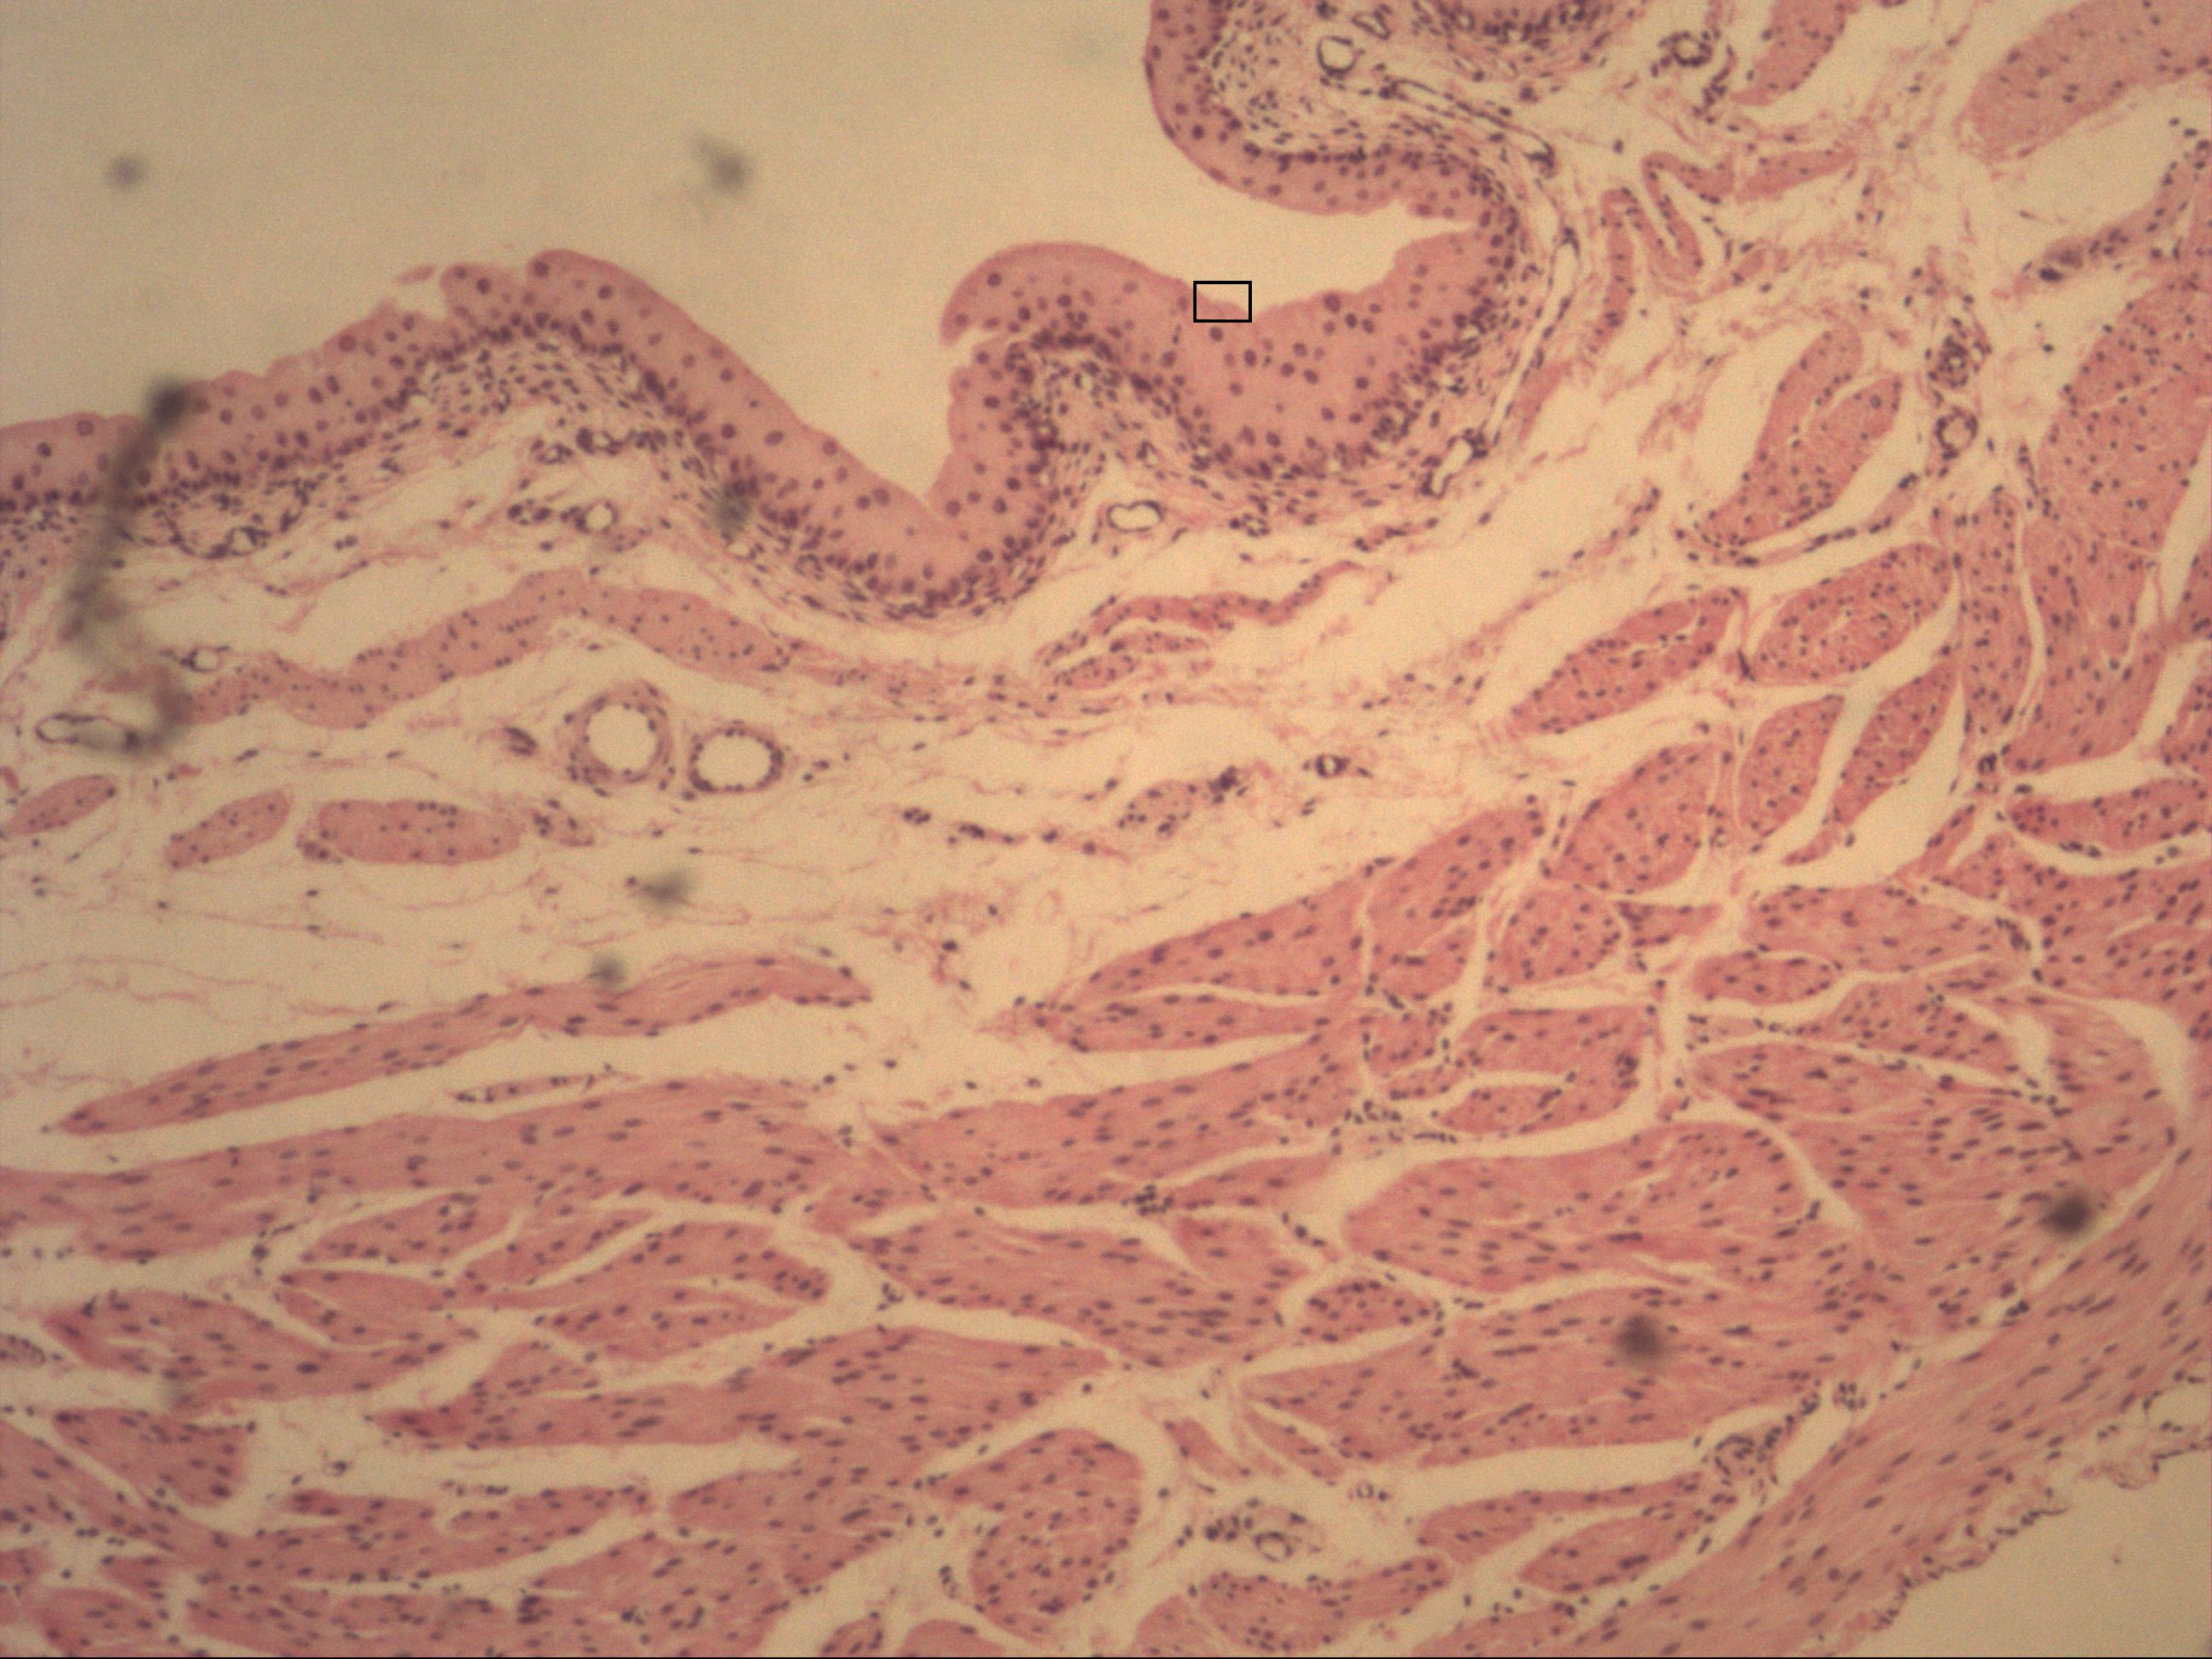

Urothel (Übergangsepithel)

Harnblase [HE]

Das Übergangsepithel findet man in den ableitenen Harnwegen. Es kann sich auf den Füllstand anpassen und besitzt eine schützende Crusta. Uroplakine und disquidale Vesikel kräftigen diesen Schutz.